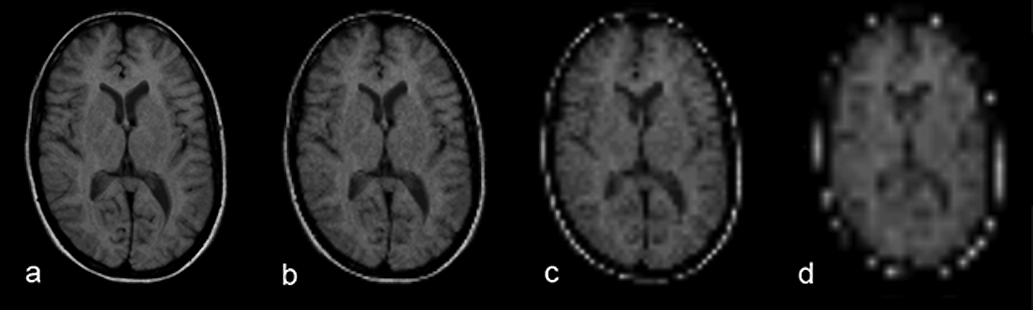

The sometimes blurry features of these im­ages are caused by the averaging of dif­fe­r­ent struc­tu­res. This is known as partial vol­ume effect. The smaller the pixel size, the better will be the suppression of partial volume ef­fects (Figure 09-05).

Figura 09-05:

Spatial resolution and partial volume effects: matrix size (a) 256×256, (b) 128×128, (c) 64×64, and (d) 32×32. Due to the partial volume effects, anatomic details disappear.

Simulation software: MR Image Expert®

However, the bigger the voxel size, the better will be the signal (and signal-to- noise). In general, the signal-to-noise is the determining factor for the final voxel-ver­sus-pixel size.